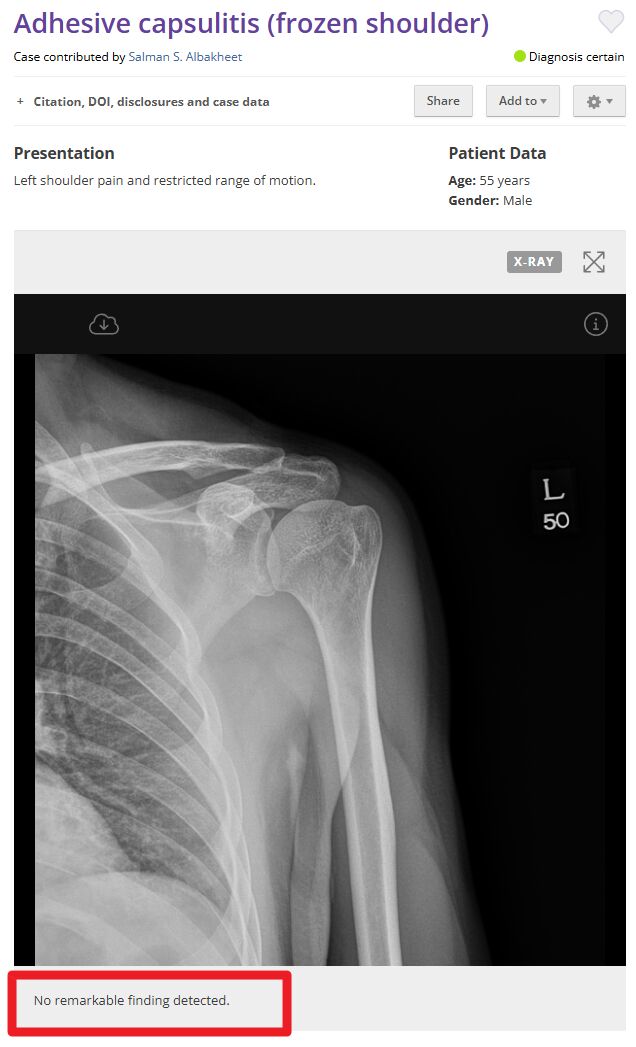

正確(A) 黏連性肩關節囊炎(adhesive capsulitis)

frozen shoulder的X光不會有明顯異常

題目也說ER減少,與frozen shoulder的症狀一致

圖片來源:https://radiopaedia.org/cases/adhesive-capsulitis-frozen-shoulder-3、https://bmjopenquality.bmj.com/content/9/1/e000550、https://shoulderelbow.org/2016/11/21/calcific-tendinitis-calcifying-tendonitis/、https://universityorthopedics.com/what_hurts/shoulder_arthritis.html